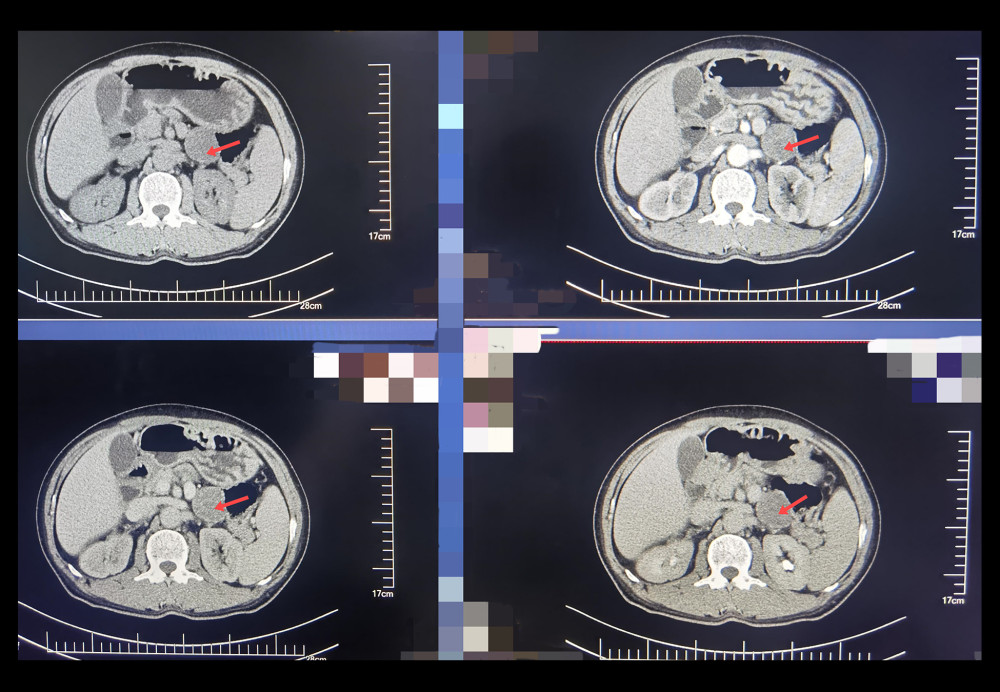

Abdominal CT (Figure 1) revealed a well-defined, 3-cm mass between the lower margin of the pancreas and the left lateral ramus of the adrenal gland; the right adrenal gland was normal. Although the radiology report did not document Hounsfield unit values, enhancement patterns and location suggested an adrenal-origin lesion. MRI (Figure 2) further characterized this as a solid-cystic mass in the same region, consistent with an ectopic adrenocortical adenoma.

Figure 1. Contrast-enhanced computed tomography axial image demonstrating a 3-cm hyper-enhancing ectopic adrenal lesion (arrow) situated between the pancreatic tail and left adrenal remnant.

Figure 1. Contrast-enhanced computed tomography axial image demonstrating a 3-cm hyper-enhancing ectopic adrenal lesion (arrow) situated between the pancreatic tail and left adrenal remnant.  Figure 2. Magnetic resonance imaging T2-weighted coronal image showing a hyperintense mass (arrow) located between the lower margin of the pancreas and the lateral branch of the left adrenal gland.